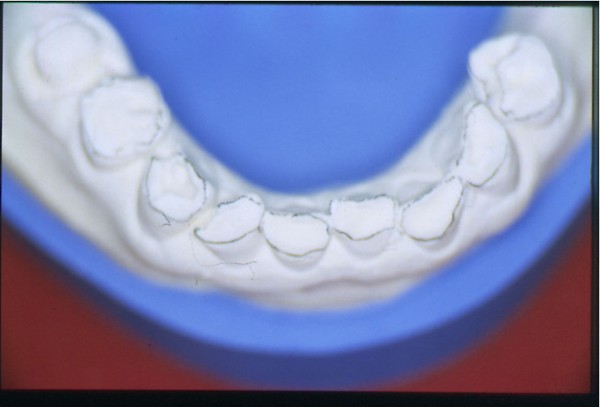

Entidades patológicas como el bruxismo, limitan la terapéutica odontológica y las certezas de un pronóstico favorable y prolongado en el tiempo. El strees, factor predisponente, y alteraciones morfológicas en la oclusión que impiden la disclusión de los sectores posteriores durante las excursiones de la dinámica mandibular, o factores desencadenantes. Caso Clínico Mujer , 53 años, derivado por especialista en Cirugía Máxilo Facial, con evidentes signos de hipertrofia de ambos maseteros. Clínicamente la carencia de las puntas caninas de ambos lados de ambas arcadas, nos habla de ciclos masticatorios eminentemente horizontales, tipo rumiante, donde el fenómeno de DOBLE DESGASTE de las cúspides estampadoras se pone en clara evidencia.(Fig.3 y 4 ) Ambos fenómenos(desgaste exagerado y extrusión dentaria nos habla de una invasión del espacio del maxilar superior, mediante la elevación del inferior, con las lógicas consecuencias musculares por acortamiento: Hipertrofia, acúmulo de ácido láctico, sobrecarga de los elementos tendinosos y capsulares, etc. Se le hace saber al paciente acerca de la necesidad de múltiples técnicas de Rehabilitación ANTES de llegar a reponer sus piezas perdidas. Se le pone en conocimiento de la necesidad de reponer SOLO hasta su primer molar, el que se reemplazará mediante una PREMOLARIZACIÓN, dado que el ancho de su cresta no permite reemplazar un primer molar salvo con riesgos de invadir el ESPACIO BIOLÓGICO necesario para un buen desarrollo de sus funciones. Es necesario tener en cuenta, que la pérdida de dimensión vertical por excesivo desgaste de la porción coronaria es siempre acompañada, por un descenso de las estructuras corticales, desfavoreciendo la relación CORONO/RADICULAR, lo que hace fundamental el ejercicio de unas fuerzas oclusales VERTICALES, a fin de no aumentar la movilidad de las piezas, una vez que la altura adecuada haya sido restablecida, verticalidad que solo se alcanzará mediante la implementación de una GUÍA ANTERIOR adecuada. Se estudia el caso clínicamente y se toman modelos de estudio debidamente montados en articulador semi ajustable en posición de ORC que es la única posición posible para rehabilitar, sin incurrir en alteraciones posicionales de la ATM, ni de elongaciones musculares y tendinosas que generen una nueva situación de strees muscular y empujen al sistema al bruxismo. Se analizan los modelos en forma estática y dinámica, donde se observan no solo las facetas parafuncionales de desgaste sino también la carencia de disclusión canina, patología generadora de dichas facetas, y que, Se confecciona un Encerado de Diagnóstico(Fig.A/B) a partir del cual se tallan las piezas en los modelos y se reproduce un juego completo de provisionales a utilizar durante el procedimiento clínico. (fig. 9) Se realizan las endodoncias y se refuerzan con Pernos Muñones Colados en oro, mediante los conceptos de Alineación Tridimensional correspondientes, instalándose los provisionales efectuados a partir del encerado de diagnóstico, los que cumplen con la tarea de discluir los sectores posteriores , tal como se concibió en dicho encerado.(Fig.10-11-12-13-14) Transcurridos seis meses de control, donde se verifican las funciones del sistema, dentro de un marco adecuado de ortofunción en el cual tal vez el más importante índice es el escaso desgaste de los provisorios, los que funcionan en una adecuada OCLUSIÓN en RELACIÓN CÉNTRICA y DIMENSIÓN VERTICAL ,situación esta apoyada por la presencia nocturna de una férula de Relajación, donde podemos observar y además «escuchar» al enfermo decirnos de su mejoría masticatoria y de la desaparición del «estado de agarrotamiento» que sentía en la boca al despertar, verificando que se siguen produciendo las disclusiones adecuadas en todas las excursiones mandibulares. Realizamos entonces al estudio radiológico adecuado, procediendo a instalar ocho(8) implantes roscados, tres de los cuales son insertados con una ligera elevación de ambas mucosas sinusales intra alveolarmente.(Fig.15-16-17) Transcurridos tres meses más y verificando la correcta cicatrización tomamos impresiones para realizar los abuttments de oro correspondientes, sobre los que instalamos un nuevo juego de provisionales que ya dan carga a los implantes.(Fig.18-19-20-21-22) Ahora estamos en presencia de un Sistema Estomatognático que presenta las características idoneas para funcionar, características estas que observamos permanentemente sobre todo la función de la GUIA ANTERIOR. Recién entonces confeccionamos las Restauraciones Periféricas Totales, las que serán realizadas en Porcelana sobre Oro . Se procede entonces a la confección de los sectores posteriores constituidos en este caso por tres premolares en cada hemiarcada de cada maxilar.(Fig.29-30) Se constatan la Estética, el Ajuste Cavo Superficial, El Espacio Libre Interoclusal, la Dinámica Mandibular,etc.(31-32-33-34-35-36-37-38-39-40) Evidentemente un caso exitoso no muestra las bondades de un método. Sin embargo, la casuística popular acerca de la imposibilidad de ser implantados aquellos pacientes que padecen bruxismo es tan frecuente como realizar en bruxómanos, coronas totales con oclusal metálica a fin de no permitir que las fuerzas de la oclusión destruyan nuestro «trabajo, sin tener en cuenta que no es la dureza del metal quien evita la destrucción…. BIBLIOGRAFÍA: 1-Oclusión y Diagnóstico en Rehabilitación Oral. 2-Disfunción temporo Mandibular y Equilibración Oclusal. 3-Rehabilitacion Bucal. 4-Problemas Oclusales. 5-Oclusión. 6-Oclusión. Conceptos para el Clínico. 7-Disfunción temporo Mandibular. 8-Neurofisiología de la Oclusión. 9-Gnatología.Principios y Conceptos.José dos Santos. 10-Oclusión y Rehabilitación. 11-Procedimientos Clínicos y de Laboratorio de la Oclusión Orgánica.